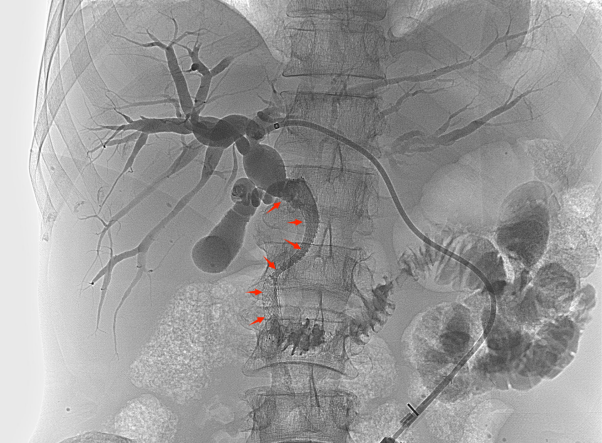

【经皮胆道支架置入术】

胆道支架置入能很好地弥补经皮肝穿刺胆道引流术的不足之处,通过在胆管狭窄/阻塞处安置金属支架,解除胆道梗阻、恢复通畅,促进胆汁入肠,改善消化功能的同时无需长期带管,显著提高了生活质量,适合短期内有效解除胆道梗阻的患者(如恶性胆道梗阻)。

低位胆道梗阻支架置入

高位胆道梗阻支架置入